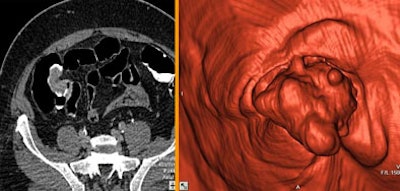

![]() |

| An 81-year-old woman presented with a positive fecal occult blood test and bleeding. A large (5-cm) adenocarcinoma was found in the right side of the colon. Endoluminal view. |